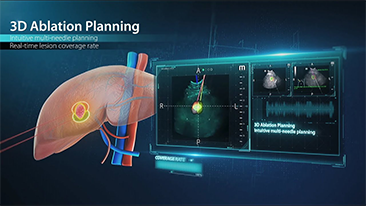

As solu??es de imagem geral Mindray Resona ajudam mĂŠdicos a obter resultados mais precisos e eficientes de diagnĂłstico e tratamento por meio de sondas de aplica??o de subdivis?es abrangentes e ferramentas eficientes de aplica??o clĂnica.